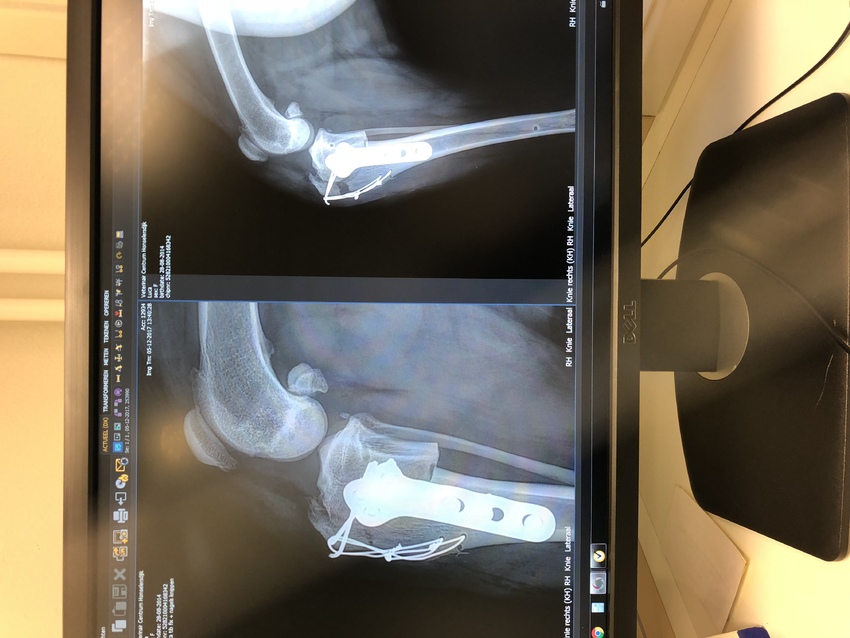

Nou ik ben geweest en een beetje gerustgesteld.. het geknak komt uit het andere eerdere geopereerde been en kan geen kwaad is gewoon waarschijnlijk een pees wat over een botje heen gaat omdat ze die poot nu meer belast, er is een controle foto gemaakt en daar was op te zien dat de breuk wie gehecht is 2 keer dubbel met ijzer hecht draad nu 5 millimeter was uitgerekt de DA was helemaal verbaast over hoe een sterke hond het is en hoeveel kracht ze in die poot heeft want die kans was eigenlijk minimaal omdat hij het 2 keer extra had vast gezet. Nu is gelukkig 5 millimeter maar minimaal en heb ik het advies gekregen om haar nog een week zo rustig mogelijk te houden en andere week dinsdag een nieuwe controle foto te maken of het niet verder is uit gerekt want dat mag absoluut niet gebeuren.. ik heb ook foto’s maar het lukt me niet om ze te uploaden

Van ogin.....kon er gelijk op lopen, heb haar wel aan de lijn gehad, thuis gewoon haar gangentje laten gaan.....zes weken aan de lijn met rustige draf loopjes, na de zes weken werd ze loops dus is er twee weken bij gekomen, daarna mocht ze los en gaan.....hier op de foto is de operatie net gedaan, het heeft zes weken nodig om bot in te kapselen.......dat is hier natuurlijk nog niet gebeurd, zes weken heeft dat nodig....vandaar de rustige loopjes......Ogin had ongelooflijk heel sterk en mooi bot....

Xbij Luca is de tplo gedaan, ook bij Bams...Luca heeft pech, nu hoop ik echt dat het verholpen kan worden het manken, toch is advies vragen aan een andere arts helemaal niet erg toch, laat jouw arts dat doen....ook is er een goede orthopeed in Roden en wel Joop Hopmans, ook daar kan jouw arts advies aan vragen wat te doen. Ik zie inderdaad dat het bot bij de tplo gebroken is, daar kan je arts niets aan doen....botzwakte kan de oorzaak zijn....ook is er al behoorlijke arthrose...heeft de arts daar wat van gezegd ?